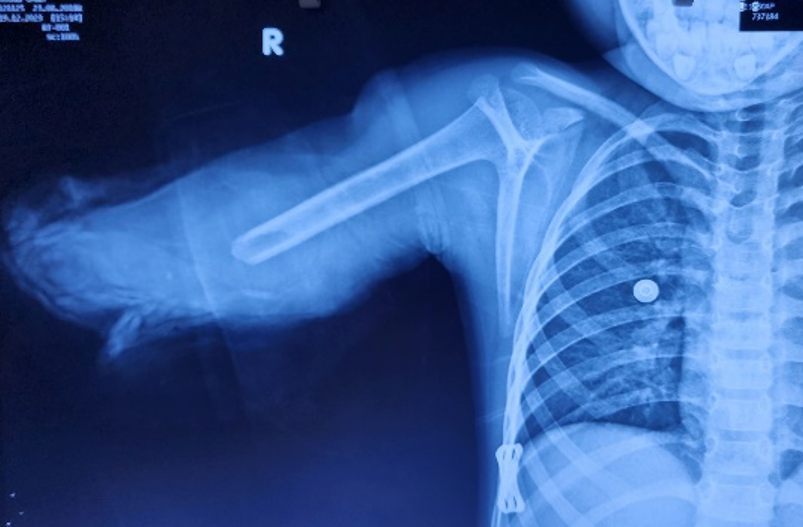

Tại đây, bác sĩ chẩn đoán bé bị đứt lìa cánh tay phải rất phức tạp và gãy xương cẳng tay. Do cơ chế vặn xoắn và giật đứt lìa cánh tay nên phần mô mềm dập nhiều gây mất đoạn mạch máu, đất cát bám vào vết thương khiến nguy cơ nhiễm trùng cao.

Tại phòng mổ thứ nhất, ê-kíp làm sạch phần cánh tay bị đứt lìa rồi kết hợp xương bằng phương pháp xuyên đinh nội tủy dưới màn tăng sáng.

Tại phòng mổ thứ hai, ê-kíp làm sạch vết thương, cắt lọc mô dập... Khi tiếp nhận cánh tay, các bác sĩ tiến hành nối vi phẫu động mạch cánh tay, tĩnh mạch, thần kinh quay, trụ, giữa, khâu các gân cơ, giải ép khoang… Bé gái được truyền tổng cộng 1.050 ml máu.

Tại đây, bé được chụp X-quang và làm thủ tục chuyển lên Bệnh viện Chợ Rẫy (TP.HCM) theo hướng dẫn của nhân viên y tế.